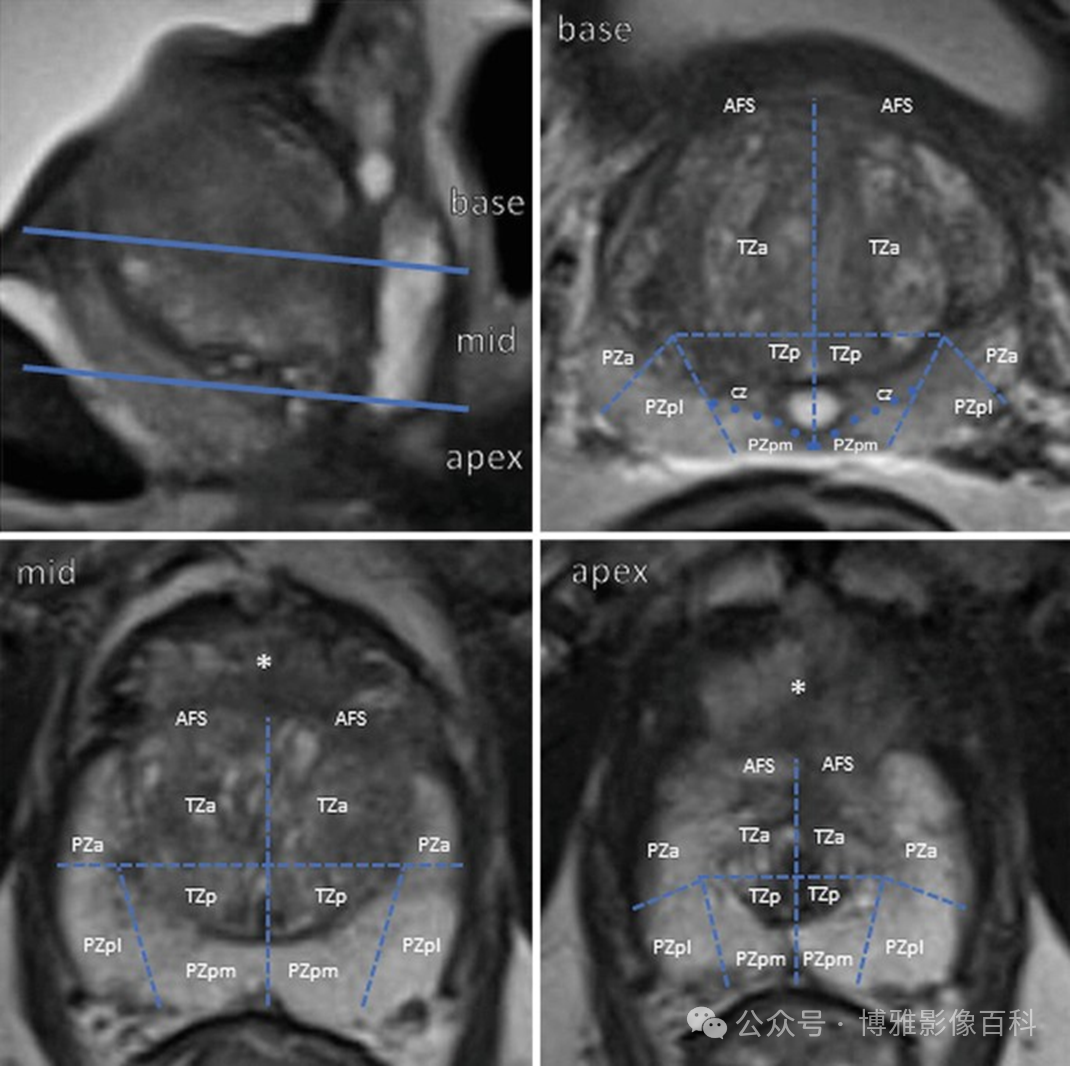

扇区解剖

PI-RADS 第 2 版中使用的扇区图使用了 39 个扇区(14 个在基底部,12 个在中部,12 个在前列腺尖部,2 个精囊和 1 个尿道括约肌)。在 2.1 版中,为基底部的左右后内侧 PZ (PZpm) 增强加了两个额外的扇区(见下图,红色)

MR 解剖学